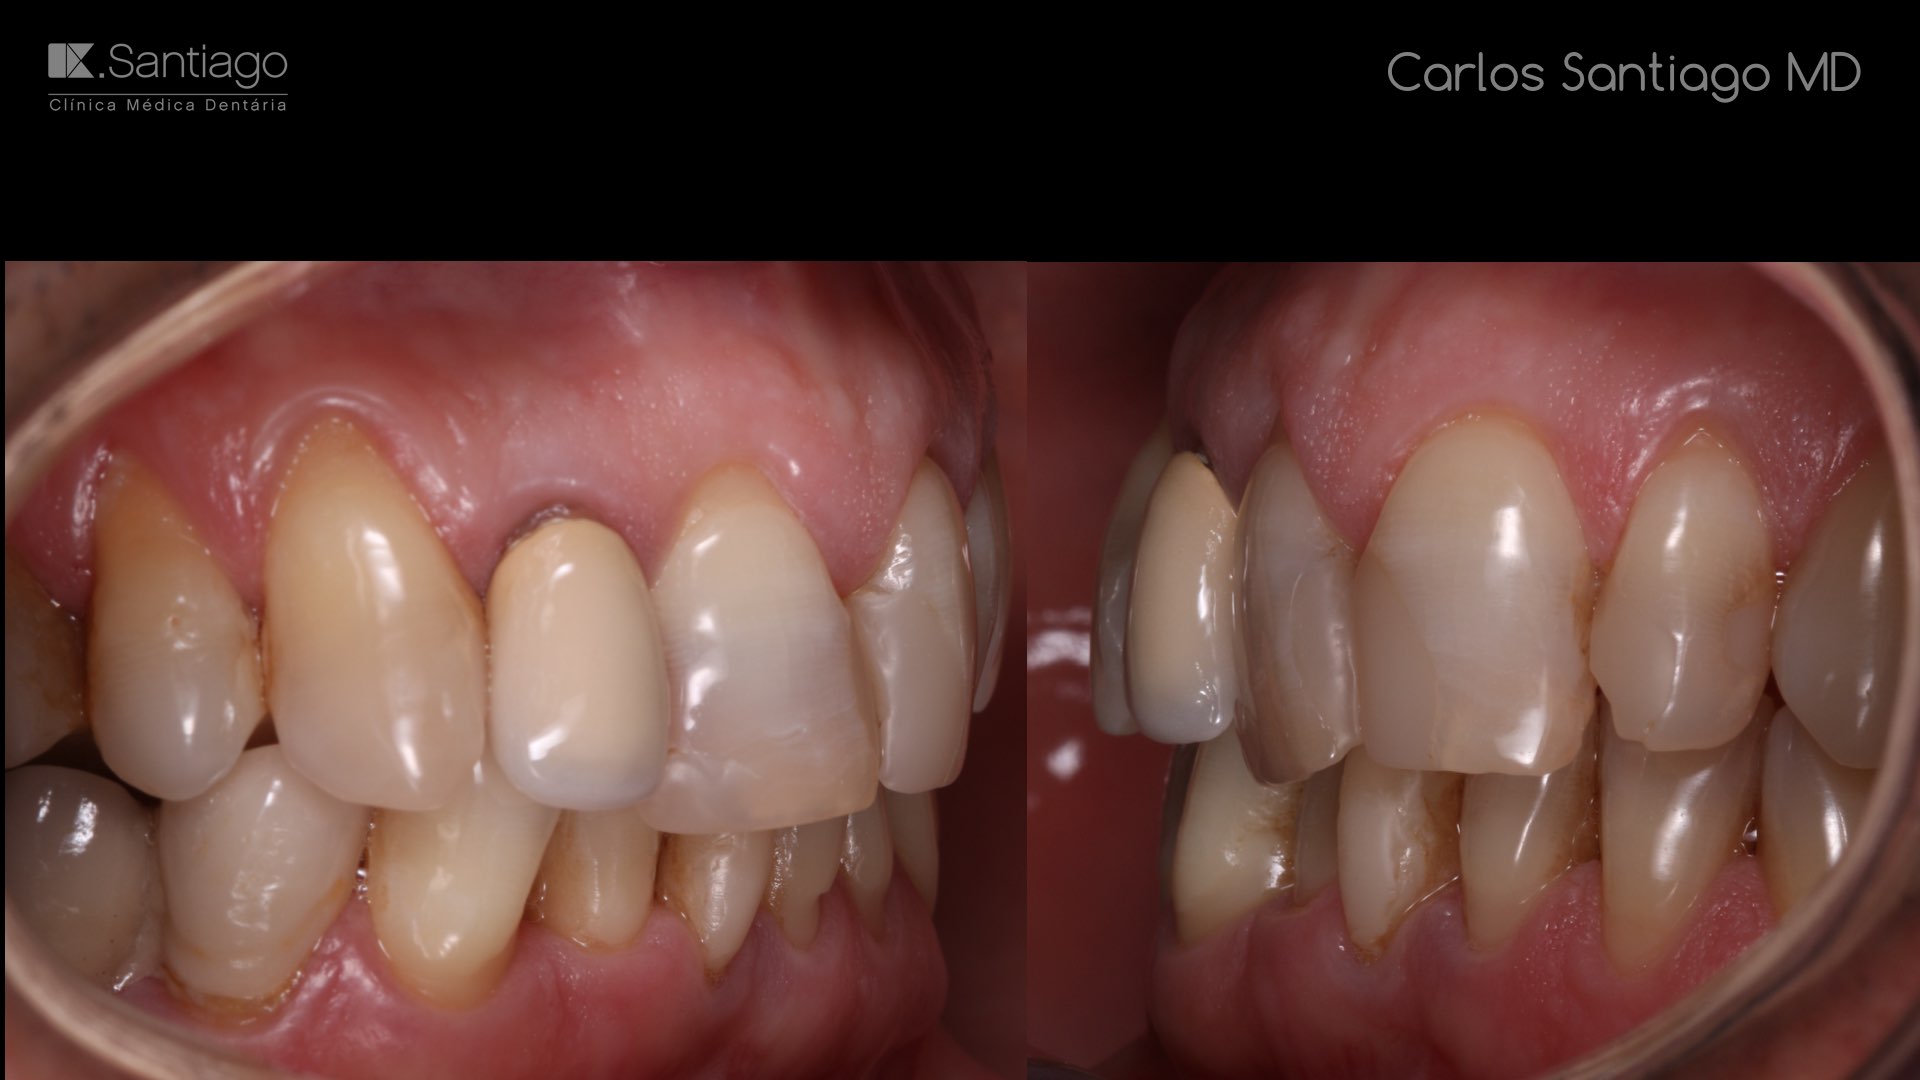

As Facetas Cerâmicas (lentes de contacto dentárias ou laminados), permitem corrigir da maneira mais estética e conservadora possível, problemas de forma e tamanho, côr e posição dos dentes, bem como substituir restaurações antigas e inestéticas.

São aderidas químicamente ao esmalte dentário de uma forma permanente, com o objectivo de melhorar a estética dos nossos pacientes.